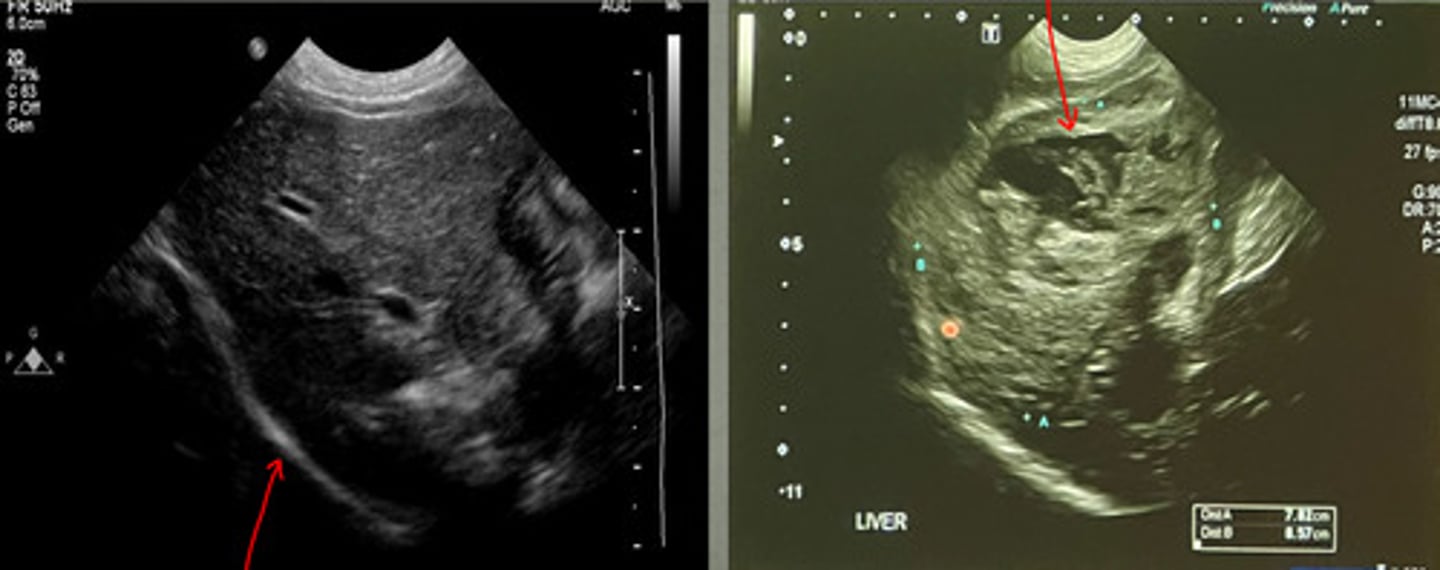

cranial border of liver

what part of the liver is this showing?

left caudal border of the liver

what part of the liver is this showing?

right caudal border of the liver

what part of the liver is this showing?

right- there is a mass on the ventral side

which of these US images of the liver is abnormal?

diaphragm

what is the red arrow pointing to in the left image?

which US image shows the normal liver?

focal mass

what focal change does this show in the liver?

nodular lesions

what is the red arrow indicating from this ultrasound of the liver?

abnormal

is this a normal or abnormal liver US?